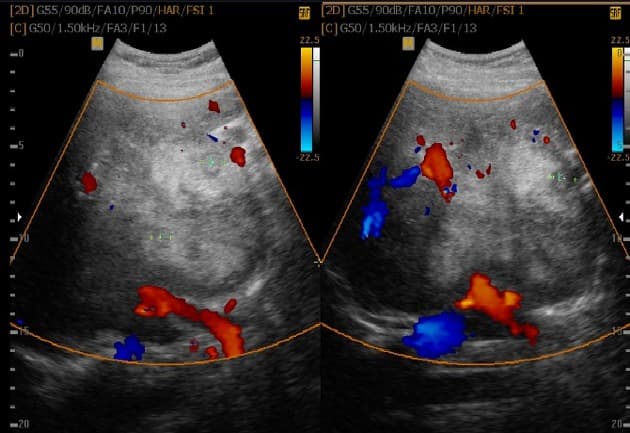

MRI gan

- Tổn thương lớn nhất nằm ở thuỳ trái gan, phân đoạn 3, có tín hiệu đồng tín hiệu (isointense) so với nhu mô gan trên hình ảnh cộng hưởng từ (MRI) trọng T1 và không giảm tín hiệu trên hình ảnh out-of-phase, điều này không gợi ý có sự hiện diện của mỡ.

- Trên hình ảnh trọng T2, tổn thương có tín hiệu đồng tín hiệu đến hơi tăng tín hiệu so với gan, với vùng trung tâm tăng tín hiệu, phù hợp với sẹo trung tâm.

- Tổn thương cho thấy tăng quang động mạch, trong đó vùng sẹo trung tâm không tăng quang, nhưng đến thì muộn thì sẹo trung tâm xuất hiện tăng quang chậm.